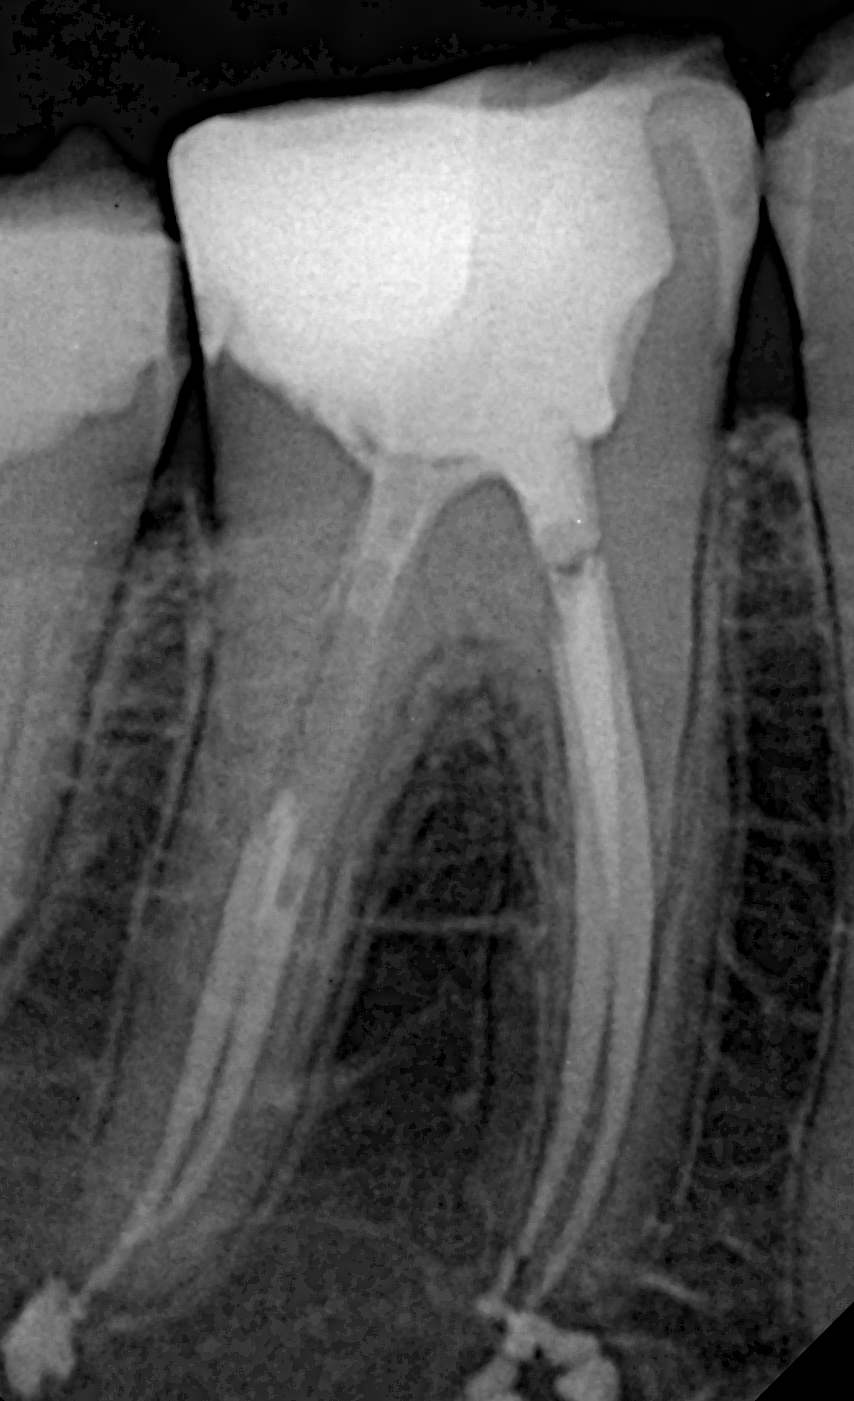

Pre-operative X-rays further confirmed the complexity:

- Complete obliteration of the mesial canals and total obstruction of the distal canals.

- Apical third calcification in the distal canals.

- Unusually long canal lengths (24 mm and 25 mm) combined with the patient’s limited mouth opening—factors that heightened the difficulty of treatment.